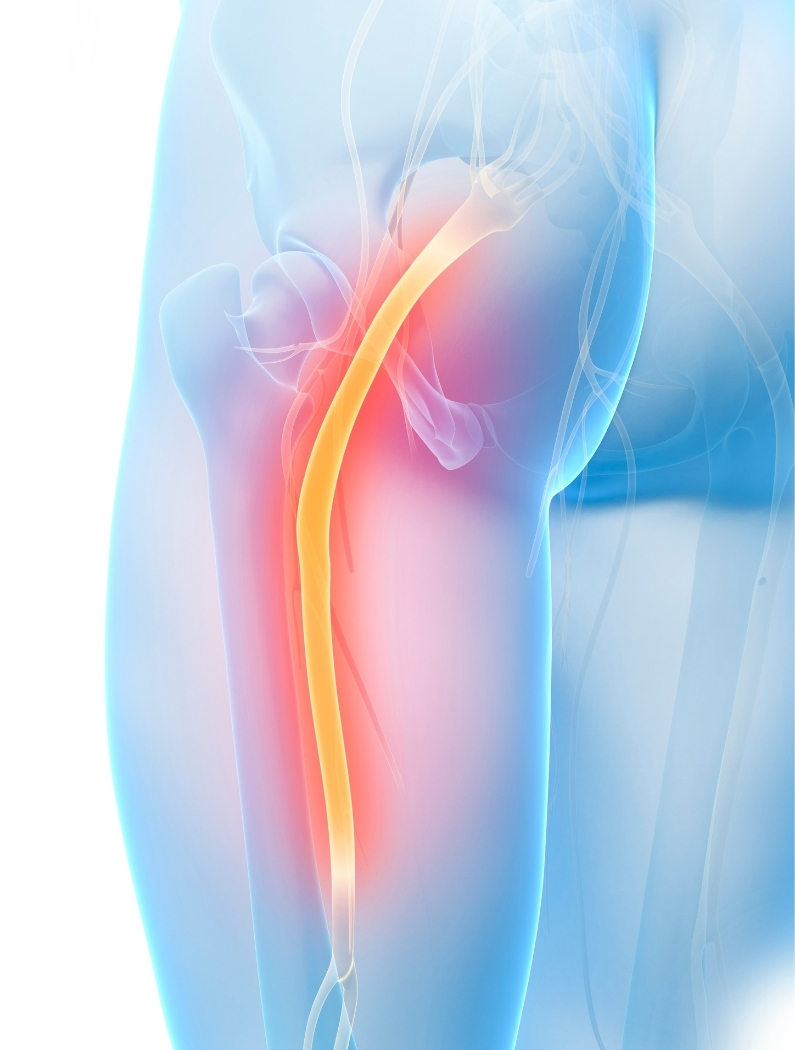

Ciática y Dolor del Nervio Ciático

La ciática se refiere a síntomas asociados a la irritación o compromiso del nervio ciático, el nervio más largo del cuerpo.

Suele manifestarse como una molestia que inicia en la zona baja de la espalda o glúteo y puede irradiarse hacia la pierna.

La ciática no es un diagnóstico único, sino una manifestación de que algo está influyendo en el trayecto del nervio ciático. Este nervio se origina en la región lumbar y sacra y recorre glúteos, muslo y pierna.

Cuando existe alteración en la mecánica de la columna, tensión muscular o cambios en el espacio por donde pasa el nervio, pueden aparecer síntomas asociados.